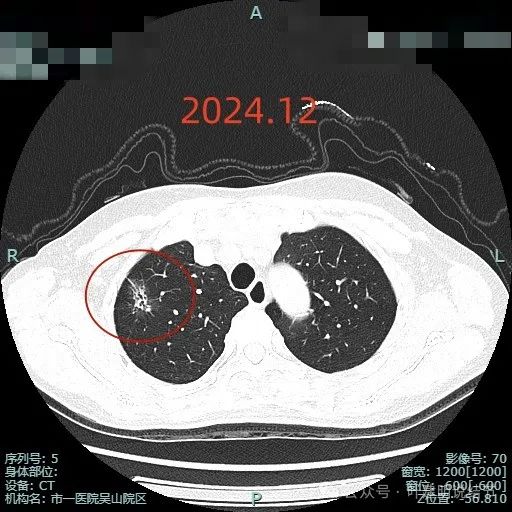

2024年12月显示出更大范围,以及更多占比的实性成分,边缘毛刺更多更典型,从影像上看已经很符合浸润性腺癌的表现了。

病灶混合密度,毛刺典型,灶内密度紊乱,表面分叶,有较多小空泡征,胸膜略有牵拉。

此视角看是典型的浸润性腺癌影像表现:混合密度、毛刺锐利典型、表面分叶、边缘不平、灶内实性成分明显且整体显得杂乱、病灶内部明显扩张的细支气管,磨玻璃成分与正常肺组织之间边界清楚,整体轮廓也清楚。